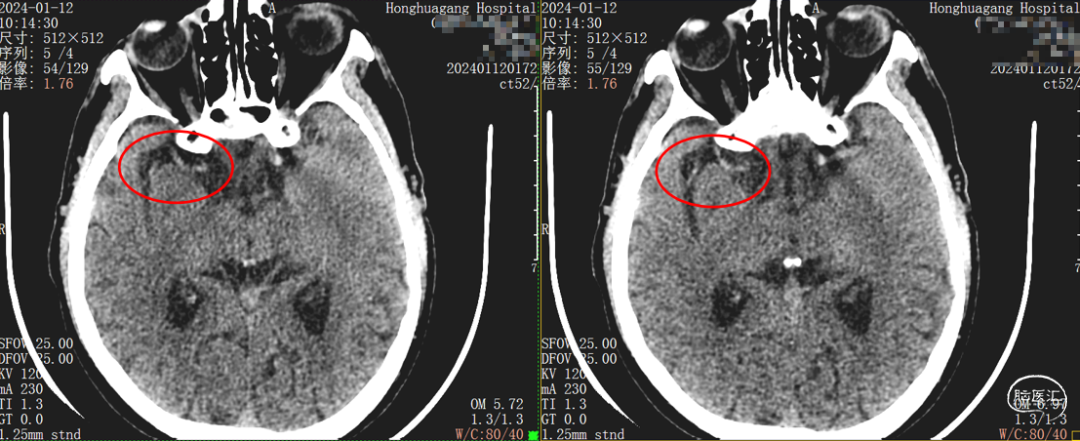

头颅CT :未见出血及梗死。

薄层CT:右侧大脑中动脉走形区可疑高密征。